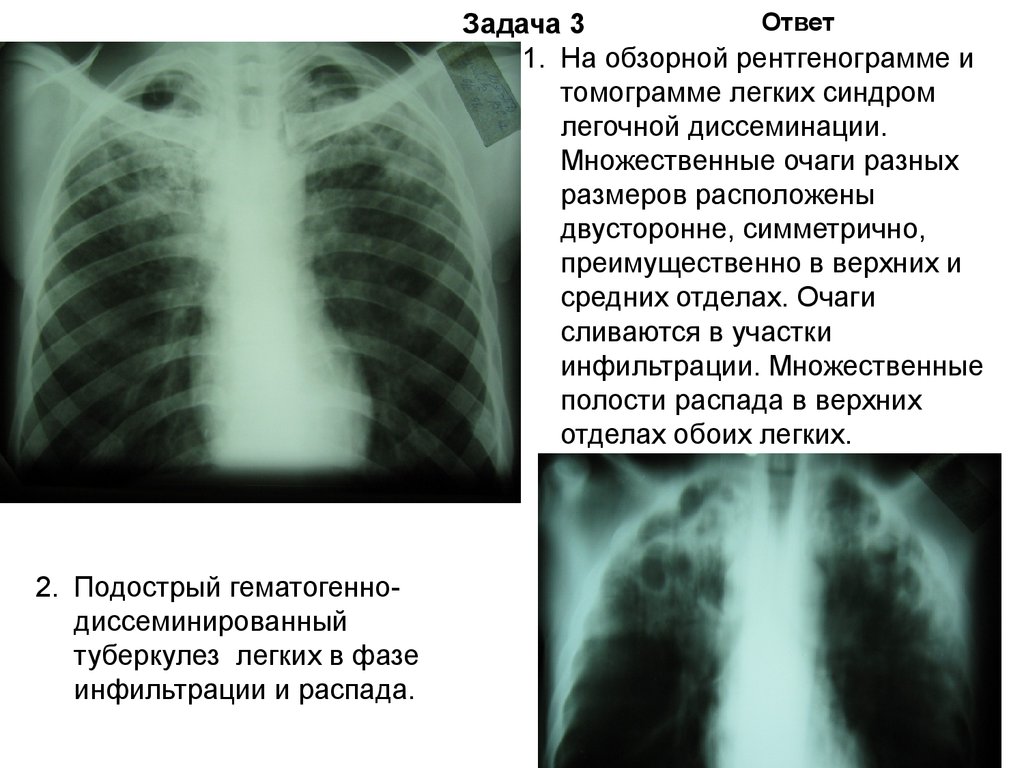

Симптомы и лечение инфильтративного туберкулеза легких

Раздел: Снимки-откровения